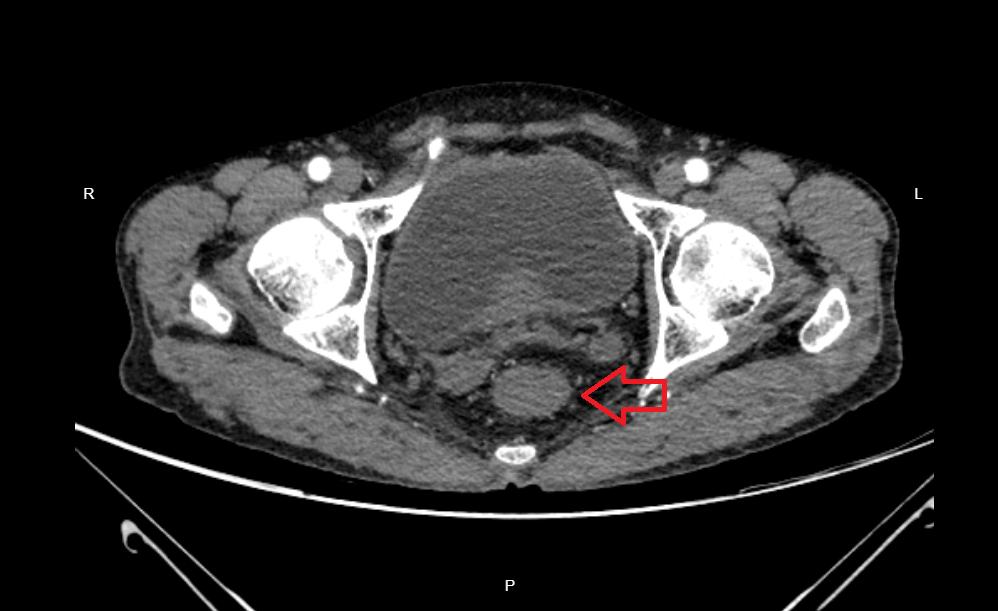

于7月8日患者按计划再次来院,经3月放化疗后增强CT及增强MRI均提示直肠上段肿物较4月明显减小,周围间隙清楚,适宜开展二期手术,7月14日手术过程中外一病区医疗团队竭力发挥腹腔镜手术优势,精准切除直肠肿瘤的同时予造口还纳,为患者避免了开腹扩大伤口或二次造口需三期手术的风险,整台手术耗时不到3小时,术中出血仅15-20ml,成功按计划完成了对患者的治疗。

为保证二期手术的成功,保障造口近端有足够长的肠段用于与直肠下段吻合,外一病区医疗团队术前细致评估影像资料,判断肿瘤范围,为患者行一期手术时选取了合适位置行乙状结肠双腔造口术,术毕转入肿瘤科进一步行放疗+卡培他滨化疗。